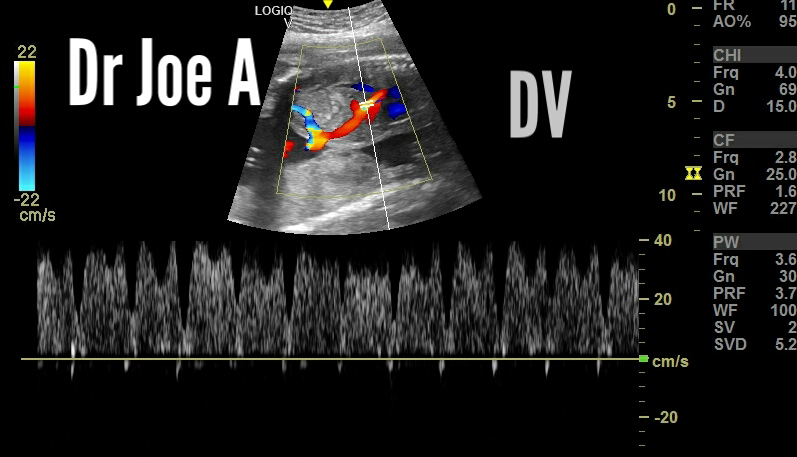

Color and spectral Doppler ultrasound imaging of ductus venosus:

Sagittal Section color Doppler images:

Spectral Doppler waveform:

Axial Section:

Doppler ultrasound examination of the ductus venosus can assess its blood flow pattern and provide valuable information for fetal diagnosis and management.